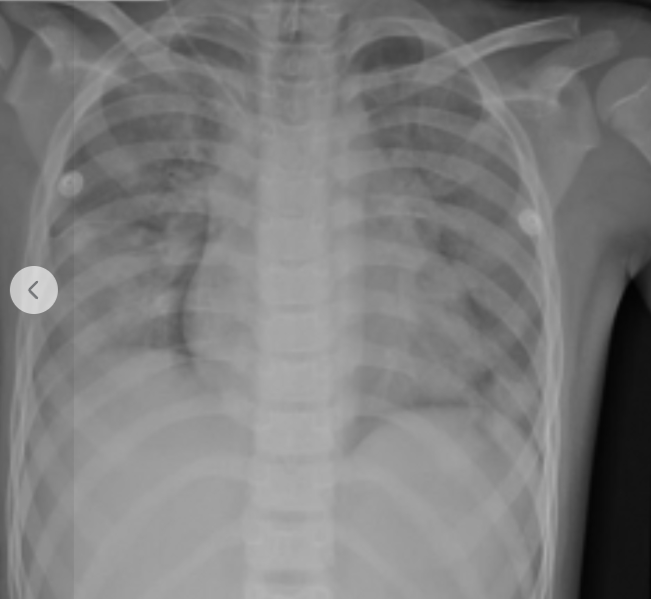

Kết quả X-quang phổi ghi nhận tổn thương lan tỏa cả hai bên phổi - Ảnh BVCC

Kết quả X-quang phổi ghi nhận tổn thương lan tỏa cả hai bên phổi; CT-Scan não – ngực – bụng cho thấy bệnh nhân bị phù não, đông đặc và thâm nhiễm hai phổi nhưng may mắn là không ghi nhận tổn thương các tạng trong ổ bụng.